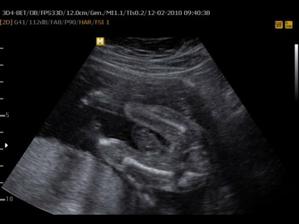

11. 3. Poradna a test cukrovky - vše dopadlo výborně. A šel čas ..... Vše probíhá OK. Jen už mládě bylo hlavinkou krásně dolů, ale otočilo se. Asi má rádo kolotoče jako mamča 🙂)) . Máme dopručený dva cviky (viz obrázek) na otočení do správné polohy. Už od 6.5.2010 můžu nastoupit na MD, ale nstoupím až ten poslední možný den 20.5.. Taky jsme s manžou domluvili tu holčičku a bude to Eliška, když to nebude Tomášek 🙂)) .